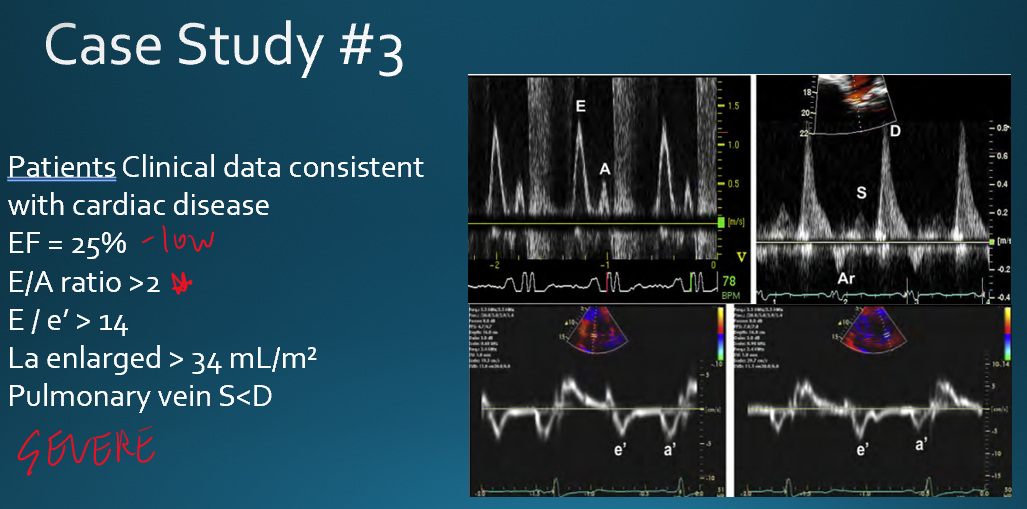

describe severe diastolic dysfunction (grade 3)

E/A ratio : E»A

LV relaxation : impaired

Atrial pressure : very elevated

atrial contraction : impaired

severe diastolic dysfunction

E : VERY high because of very elevated LAP

A : small

what diastolic pattern is shown here?

severe

deceleraion less than 150

E/A ratio : 2.78